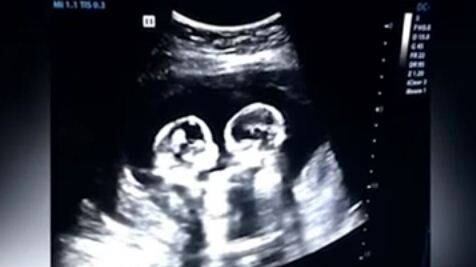

El papá de un par de niñas captó el adorable y gracioso momento en el que las gemelas parecen pelear en el útero de su mamá. Este hombre de nacionalidad china, llamado Tao, grabó la ecografía que le estaba haciendo a su esposa.

Tan solo cuatro meses de gestación tenían las pequeñas y aunque realmente no peleaban, eso parecía. En una red social china fue publicado el video y al poco tiempo se viralizó, incluyendo en los medios de comunicación, por lo que el orgulloso padre afirma: «No esperaba que mis hijas fueran estrellas de Internet antes de nacer.»

Pero esto no es todo, Tao aseguró a los medios que no solo vio a sus pequeñas «pelear» sino que en una oportunidad las encontró abrazadas.